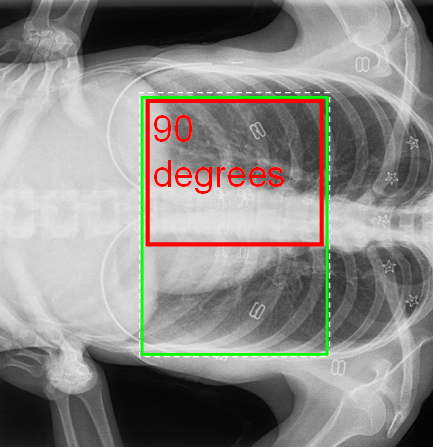

Similarly, if rotated, then the height/width remain relative to the rotated image's "text" frame of reference, giving for a 90° rotation (see below for when this would occur) this would be:

However, if the rectangle defining the area is allowed to rotate without rotation of the text, then the text and its container are mis-matched shapes, and some ambiguity arises. In these images, the green rectangle is the largest "straight" rectangle fitting within the rotated rectangle:

The above is the default behaviour of versions until now, inherited from V6, and whilst it makes some sense for the multiples of 90°, it makes no sense for other angles, and will therefore be dropped from now on. In its place will be a new "NoRotation" mode, which acts in an analogous but reversed manner to the simple rotation of an image without being image tied - i.e. the text will retain the same size and shape as if the image were NOT rotated. Like the simple rotation, this requires definition and use of a "rotation point", and the same RotationPoint and RotationCentre(X/Y) properties but in this case the definition will be in image pixel coordinates.